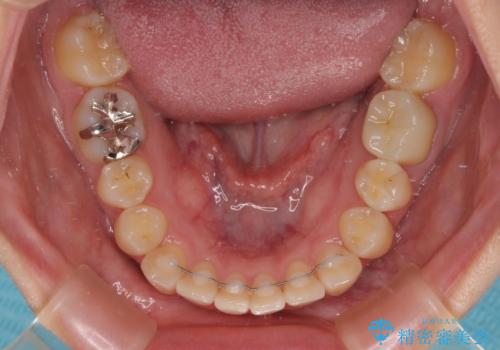

- 前歯のクロスバイトを改善したいとのことで来院された患者様です。

マウスピース矯正では前歯の神経への負担が大きいことを懸念され、ワイヤー装置による矯正治療を行うこととしました。

クロスバイトが改善する際は、前歯しか接触しないため、痛みがあったり食事が取りにくかったりと、不便な時期がありますが、1年強の短期間で無事に治療を終えることができました。